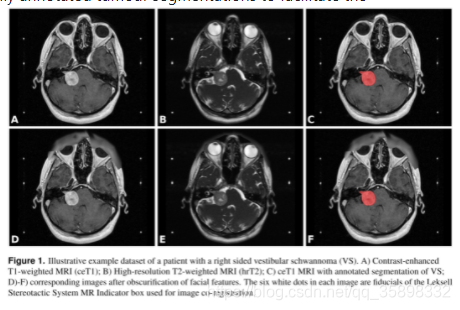

1、domain adaptation做分割(242个病人,图像数目前未知,两种模态ceT1/hrT2,都有segmentation label,配准后能评估dice),图像如下图所示:前两列为两个模态,第三列是label示意,目前还没申到数据集,根据数据集描述在两个模态上都有segmentation label,3D数据

其他有用的信息:给了affine的file,在后面跑affine baseline的时候学出来的affine matrix可以和它做一个比较,能够看affine效果

目前的担忧:感觉形变不是很大,所以可能无法体现deformable优势